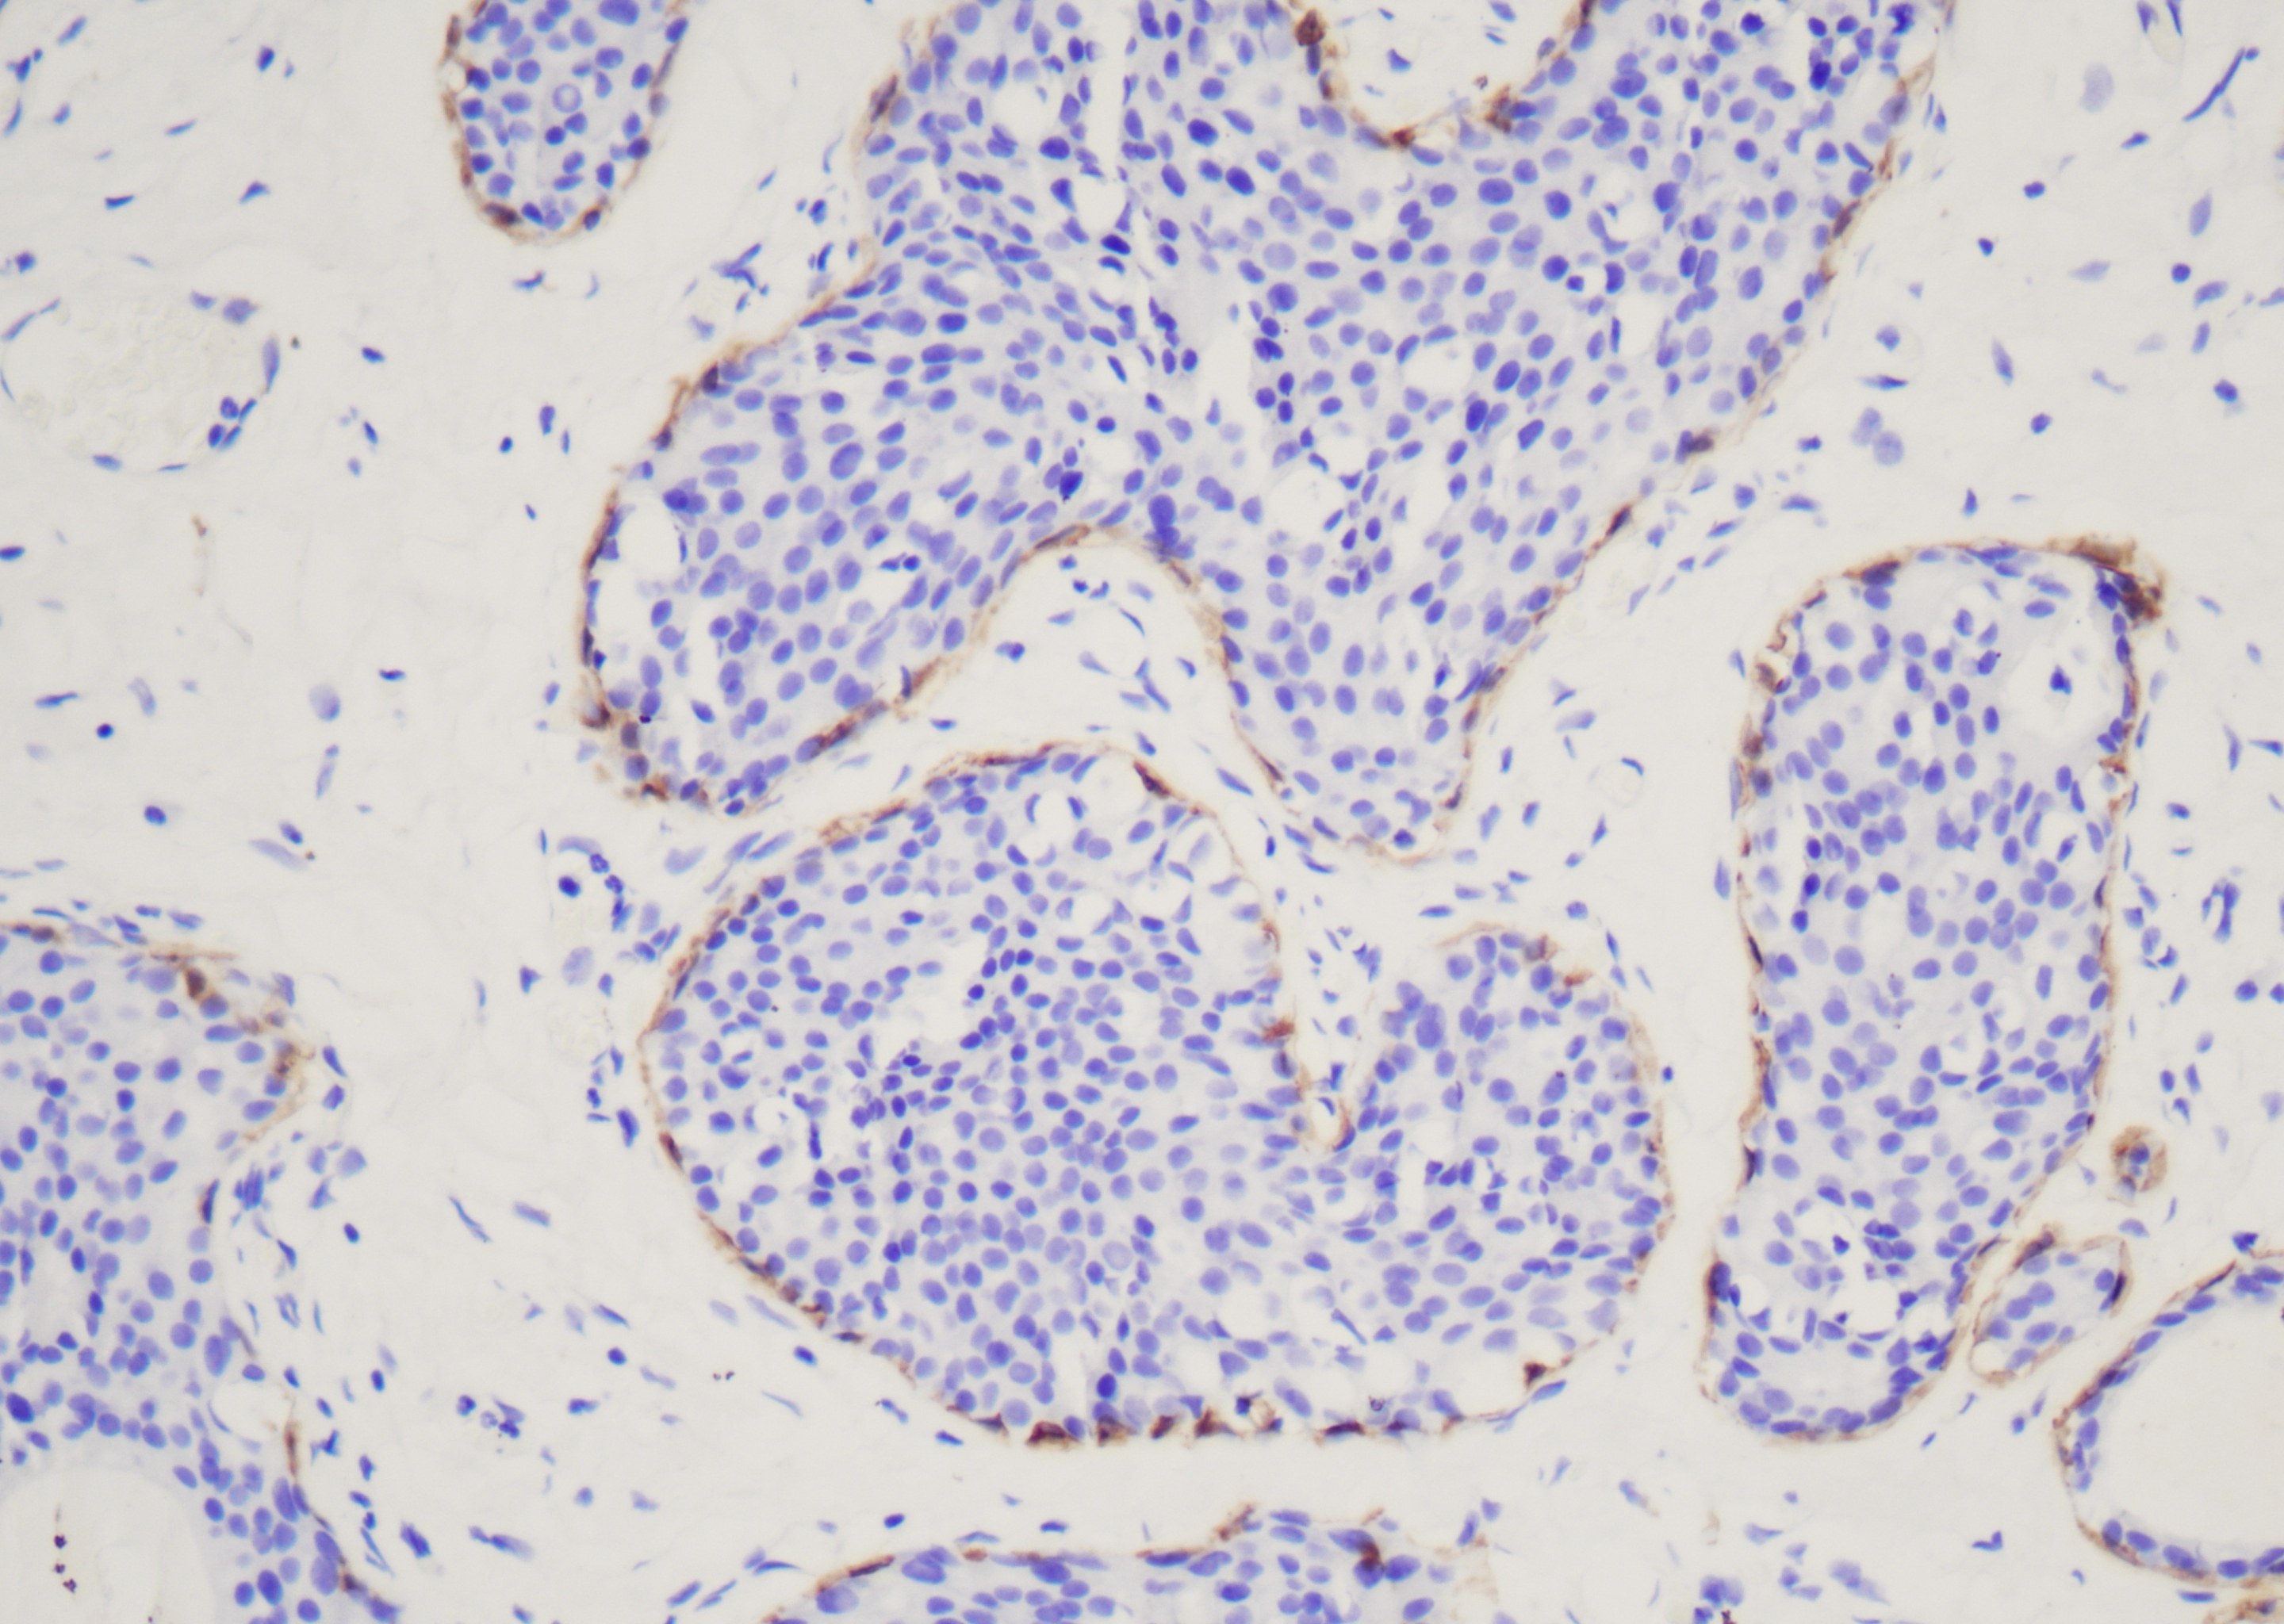

本试剂盒可检测通用的鼠源或兔源一抗,试剂盒中阻断剂可阻断组织片内源性过氧化物酶,一抗与切片中的靶抗原形成抗原抗体复合物,一抗后试剂封闭非特异性蛋白及提高结合效率,超敏酶标羊抗小鼠/兔IgG聚合物与抗原抗体复合物中的一抗结合。DAB A液和DAB B液混合成DAB显色液,超敏酶标羊抗小鼠/兔IgG聚合物中的HRP催化DAB工作液在抗原部位棕色沉积,苏木素复染定位细胞核。